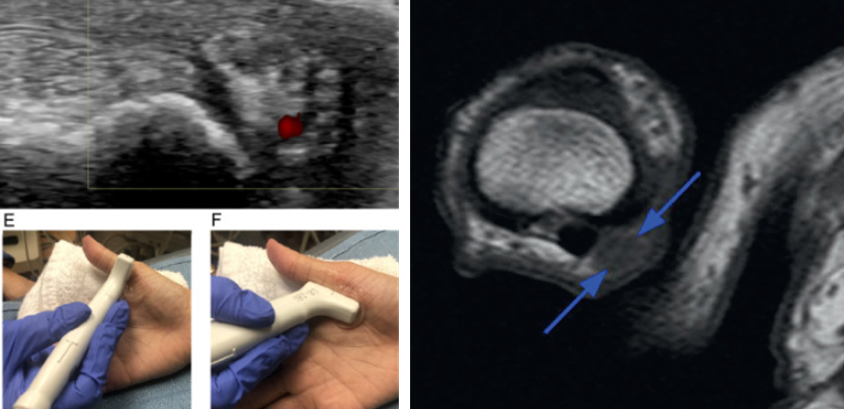

초음파나 MRI로 신경 주위 섬유화, 혹(결절) 등 구조적 변화를 확인할 수 있습니다.